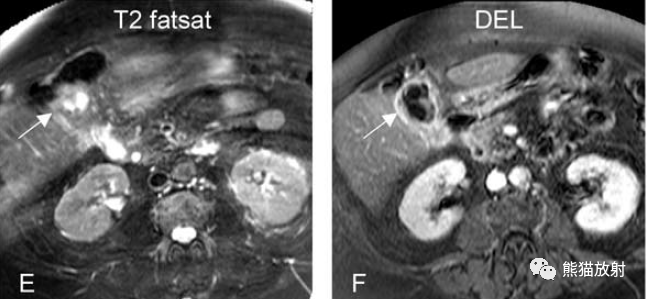

膽囊癌。A~D圖:上方層面,表現(xiàn)如上所述,形成腫物侵及肝臟。E、F圖:下方層面示膽囊壁不規(guī)則增厚,明顯不均質(zhì)強(qiáng)化。

另一例膽囊癌,T2WI及增強(qiáng)延遲期顯示膽囊壁不均勻增厚并明顯強(qiáng)化。